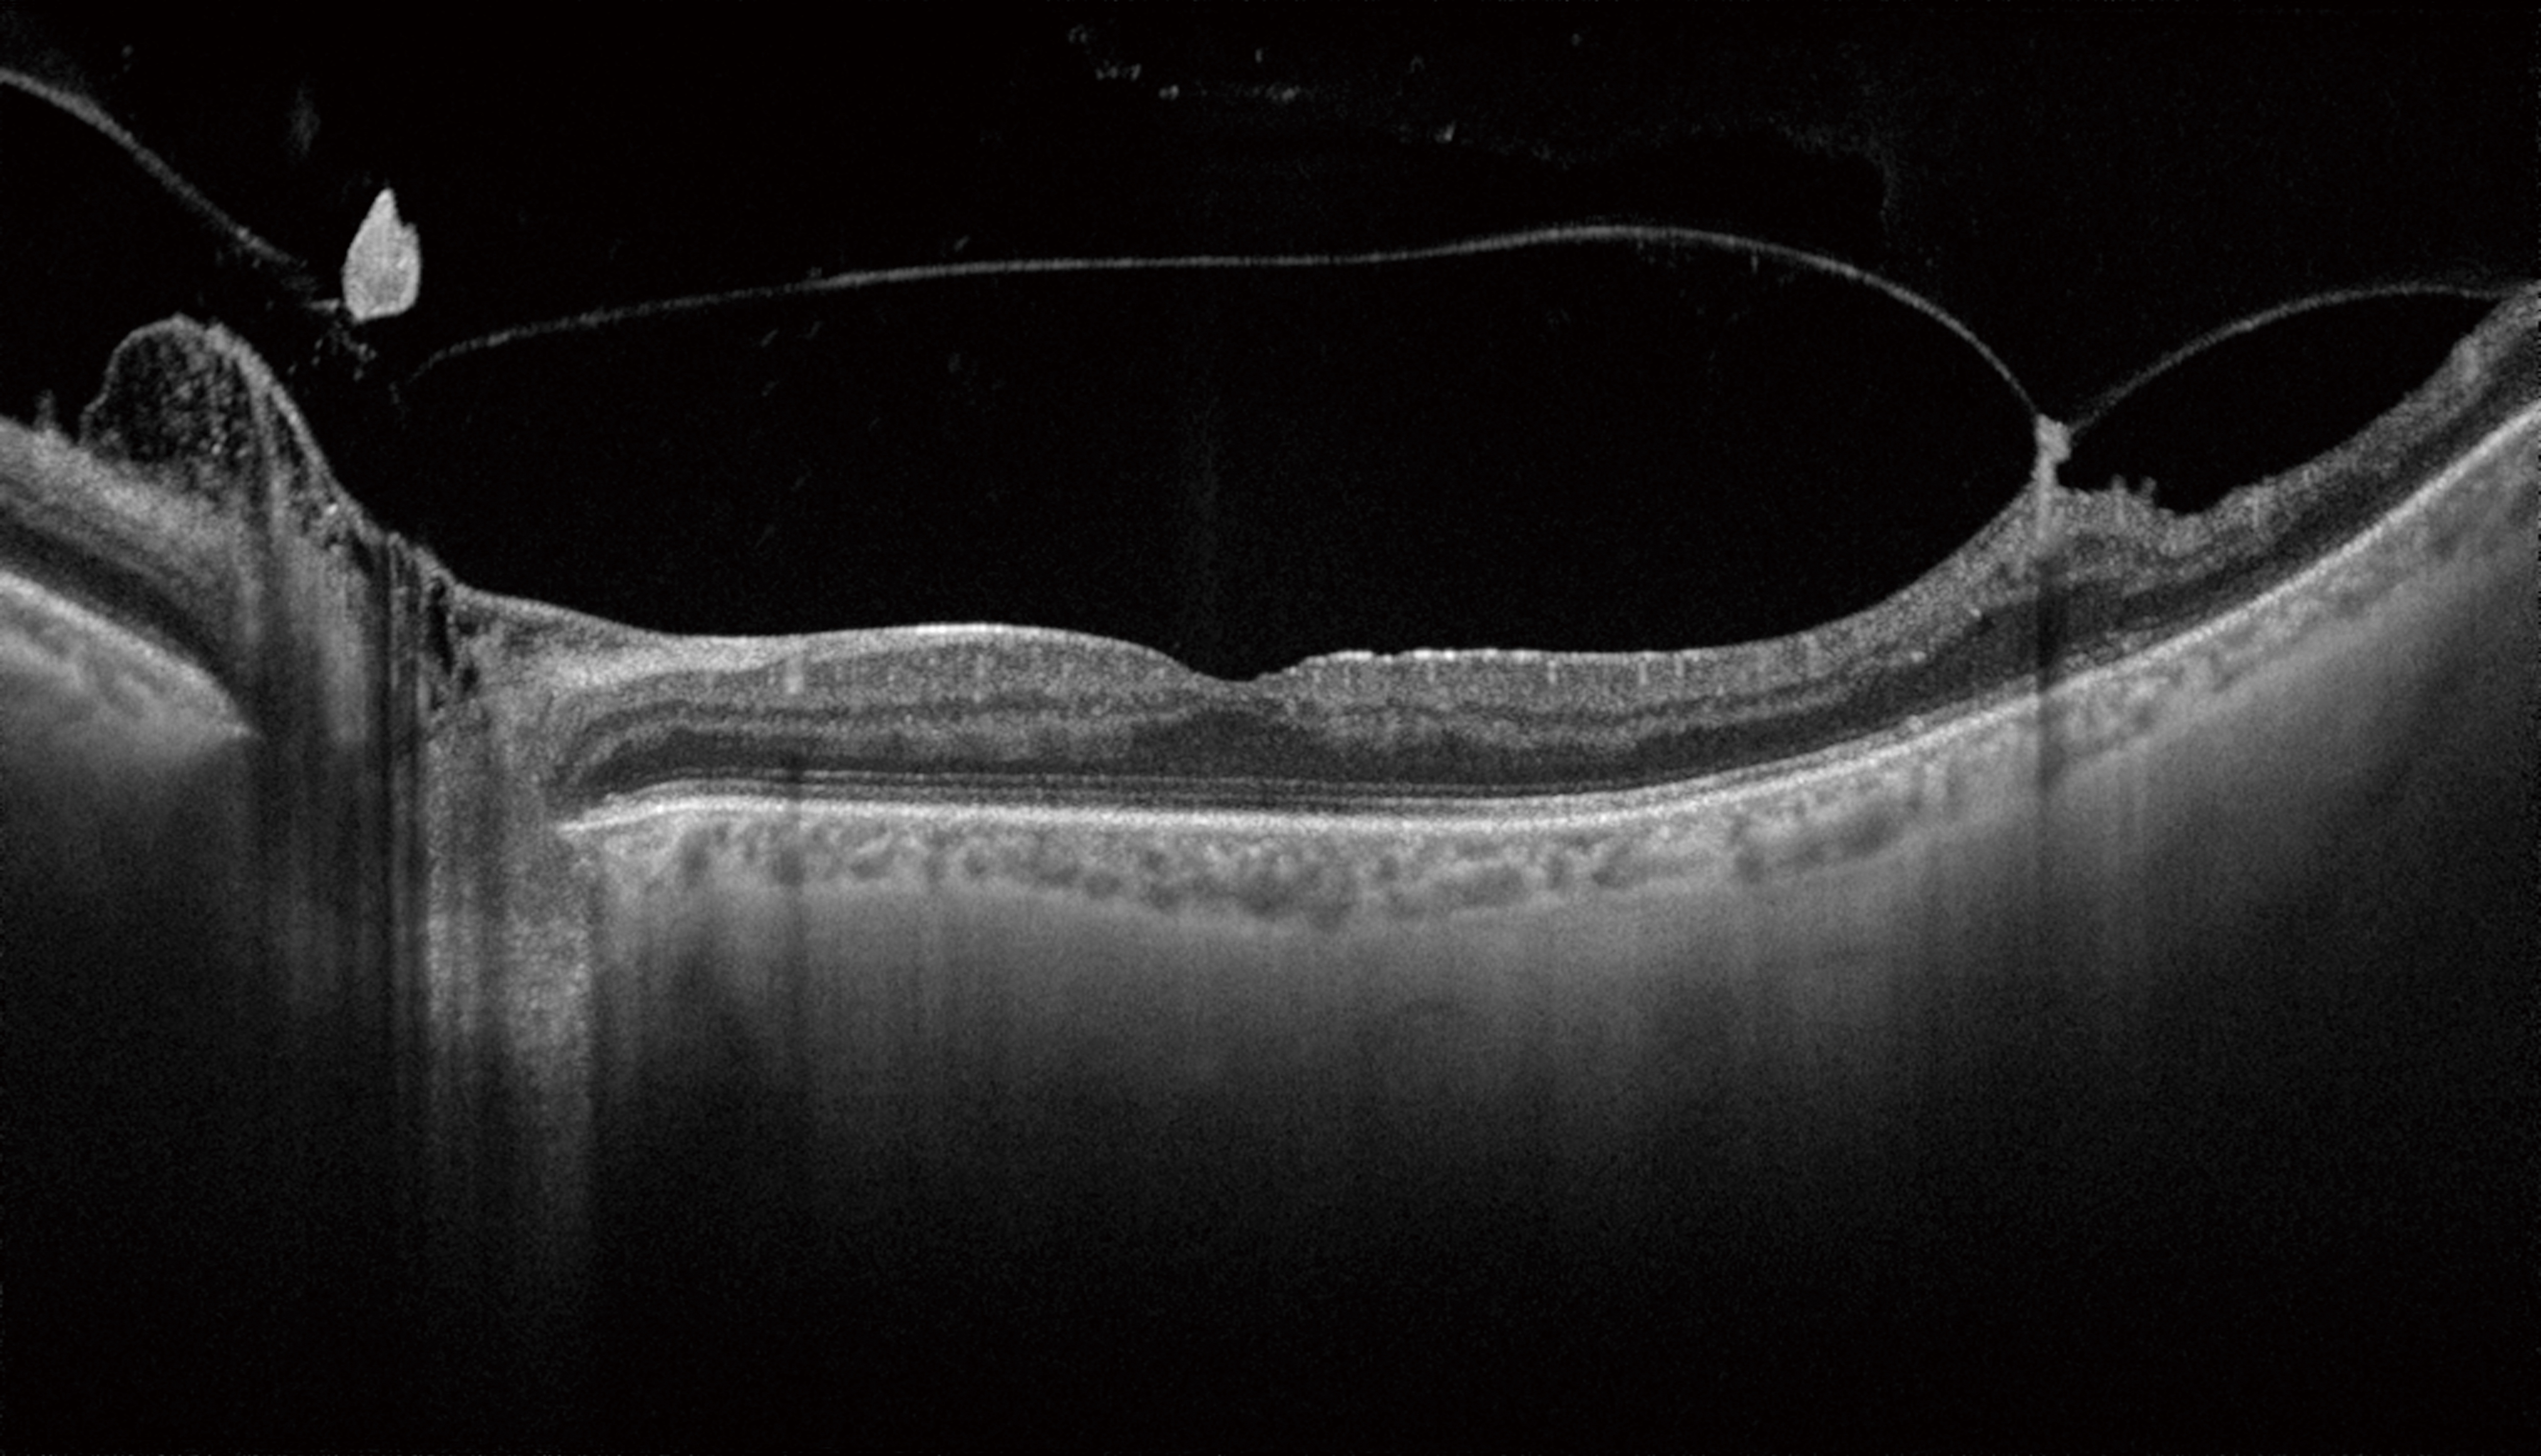

Triton с технологией Swept Source благодаря скорости сканирования 100 000 Асканов/сек и длине волны 1,050нм обеспечивает чёткую и детальную визуализацию глубоко лежащих слоёв сетчатки, в том числе хориоидеи и склеры1.

- Улучшенная визуализация глубоких слоев заднего отрезка, включающих хороидею и склеру за счет инфракрасного источника света 1050 нм, в том числе в случае помутнений в оптических средах

SWEPT source и длина волны сканирования 1050 нм

Уникальное сочетание нового механизма получения ОКТ-снимков SWEPT Source и сканирующего луча в инфракрасном диапазоне (1050 нм) позволяет получить качественный ОКТ снимок структур заднего отрезка глаза: стекловидного тела, сетчатки, хороидеи и склеры – на одном скане. Эта особенность сокращает время исследования за счет отказа от получения дополнительных снимков для получения снимков высокой четкости.

Прибор позволяет получать ультраширокие сканы 12 × 9 мм и 12 × 12 мм, позволяющие оценить состояние диска зрительного нерва и макулы за одно исследование.

- Глубина сканирования: 2,5 мм

- Продольное оптическое разрешение: 3 мкм